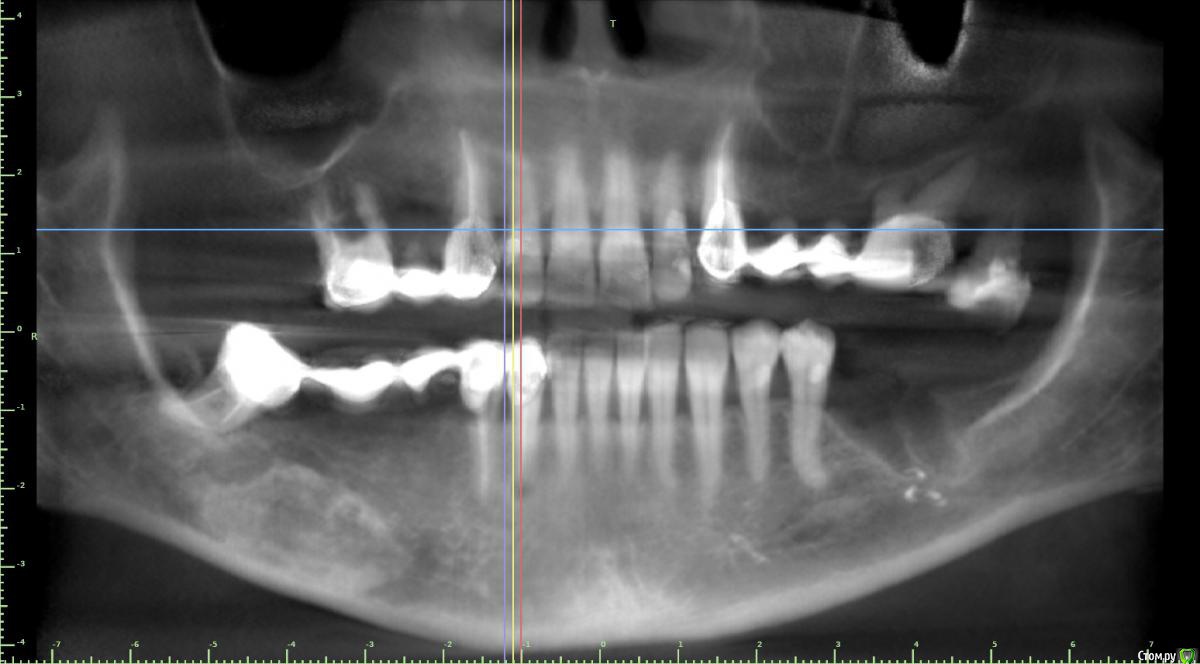

Дмитрий Л. Опубликовано 23 мая, 2018 Поделиться Опубликовано 23 мая, 2018 (изменено) 4 квадрант Судя по срезу кт - костный рисунок, хотелось бы больше срезов. Изменено 23 мая, 2018 пользователем Дмитрий Л. Ссылка на комментарий

Борис80 Опубликовано 23 мая, 2018 Автор Поделиться Опубликовано 23 мая, 2018 какое то образование с четкими границами, достаточно большое, по структуре напоминает кость, но имеет четкий контур...в пределах челюсти, жалоб не предъявляет, с правой стороны(шрам на шее) была резекция подчелюстной слюнной железы, 3д моделировка снаружи: Ссылка на комментарий

Борис80 Опубликовано 23 мая, 2018 Автор Поделиться Опубликовано 23 мая, 2018 были бы более скромные размеры, я бы принял подобное за секвестры, но тут 3 см... Ссылка на комментарий